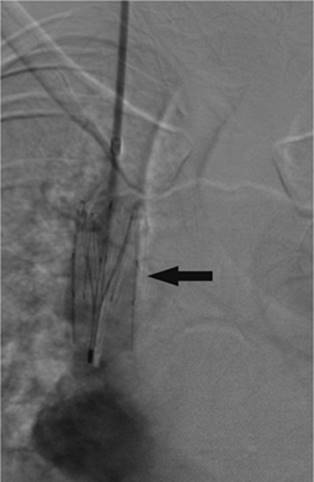

Figure 35.3. Patient with diverticular disease and mesenteric abscess. A: Close proximity of bowel loops (arrows) to the 4-mL fluid collection (asterisk). B: Required CT guidance for drain placement (arrow).